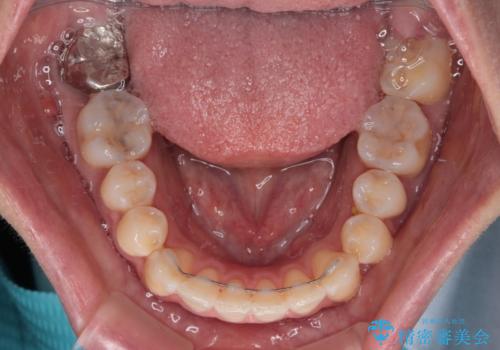

八重歯と開咬の抜歯矯正 ワイヤー装置を併用したインビザライン矯正治療

- 咬み合わない前歯と八重歯などのデコボコを気にして来院された患者様です。

上下前歯の位置を比較すると上顎が前方にあり、デコボコ改善でより上顎が前方に行く可能性があります。

開咬の改善にはインビザラインが有効であり、インビザライン単体での治療を検討しましたが、上顎前突を回避するために上顎左側第一小臼歯抜歯を行うこととしたため、補助装置とワイヤー矯正を併用した上で、インビザラインによる矯正治療を行うこととしました。

インビザライン矯正治療では、臼歯の圧下による前歯部の早期接触が大きな問題となっています。開咬では、その臼歯圧下を逆手にとって前歯部の非接触を改善させることができます。